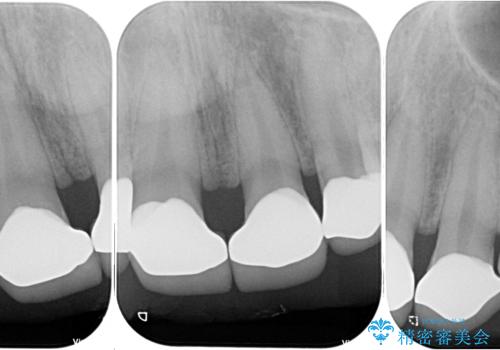

- 歯の欠損による前歯のすきっ歯を気にして来院された患者様です。

矯正治療かオールセラミックか、治療の選択がありましたが、熟考の末オールセラミッククラウンにて補綴することとしました。

ひとつひとつの歯の幅は非常に大きくなりましたが、手っ取り早く隙間が改善されたとのことで、大変満足していらっしゃいました。